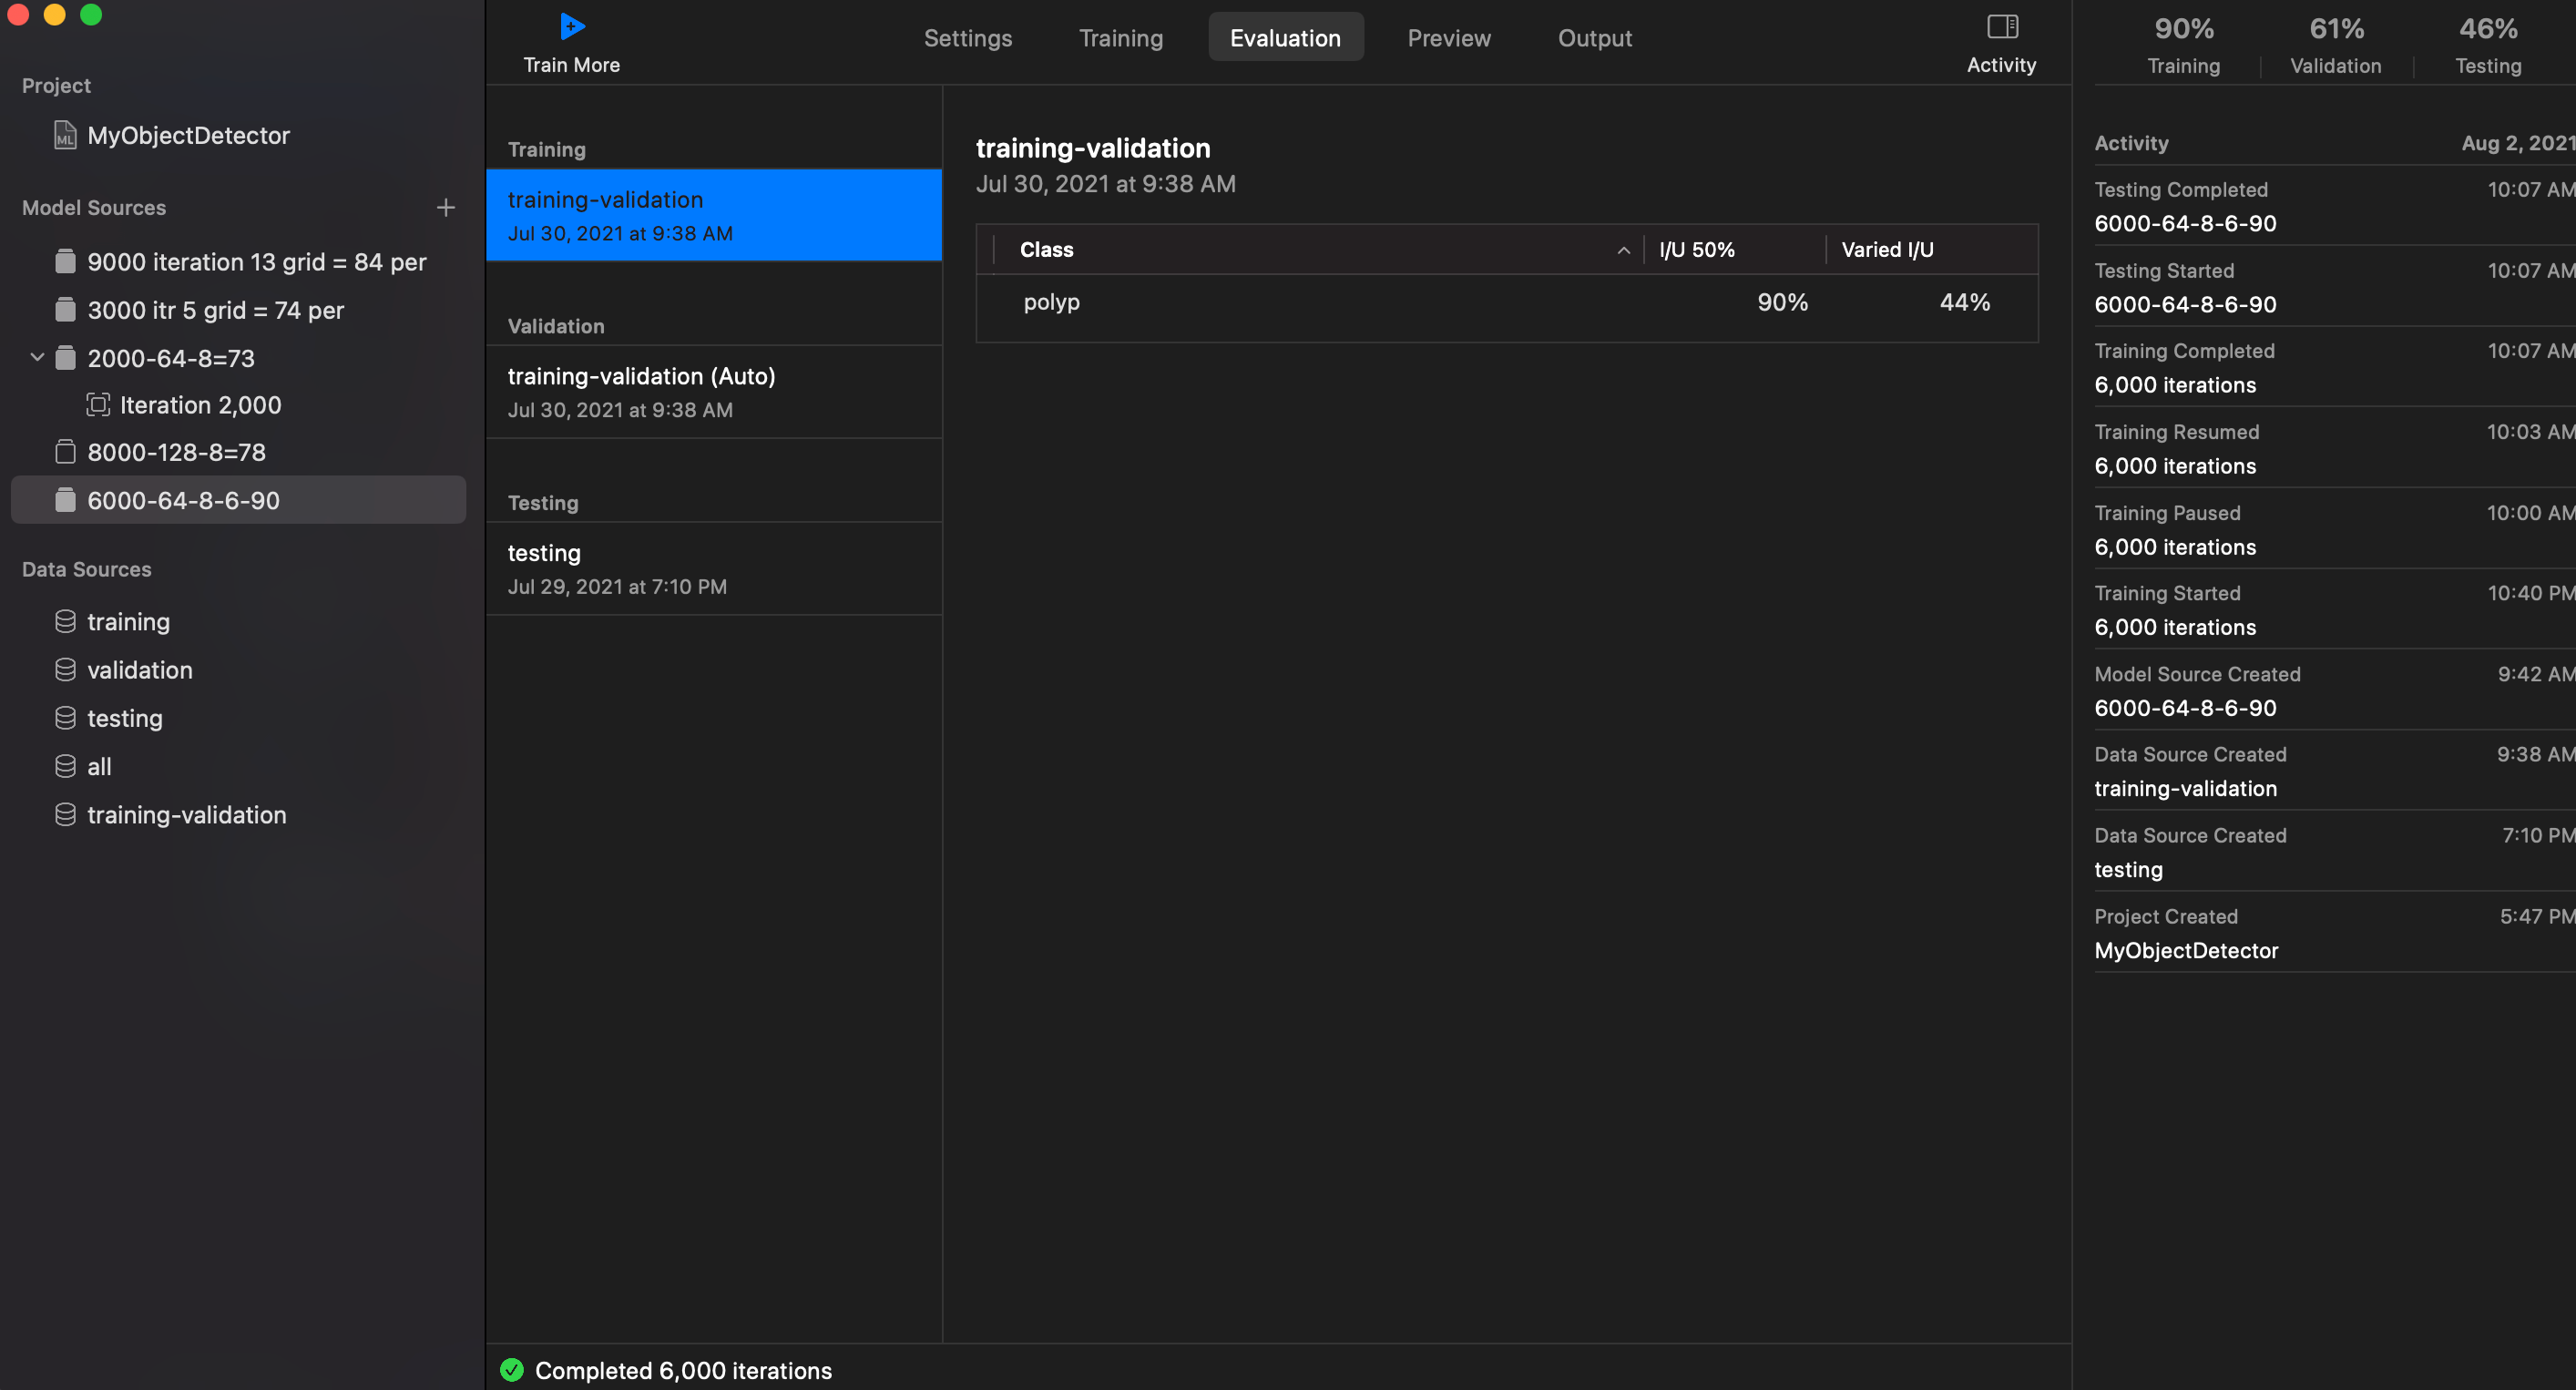

I/U 50%: 90%

Training: 90%

Training: 71%

Training: 46%